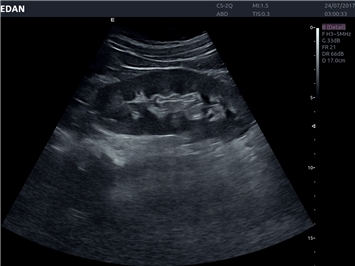

B-режим, Двухмерное сканирование:

Да

Общая визуализация:

• Превосходное качество визуализации в любых условиях